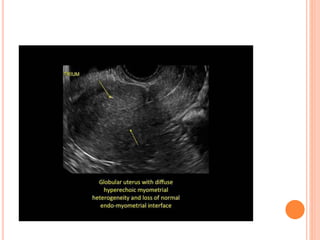

ULTRASOUND  Sonographic featuresof adenomyosis are variable and may be absent.  The reported sensitivity and specificity of trans- abdominal ultrasound are 32-63% and 95-97% respectively 7.  The spectrum of findings includes:  Normal appearing uterus  Focal or diffuse myometrial bulkiness, typically of the posterior wall .  Thickening of the transition zone can sometimes be visualised as a hypoechoic halo surrounding the endometrial layer of ≥12 mm thickness

 Subendometrial echogeniclinear striations  Subendometrial echogenic nodules (specific sign)  Small myometrial cysts / sub endometrial cysts (specific sign)  Heterogeneous echogenicity (heterogenous myometrial echotexture)  hyperechoic: islands of endometrial glands  hypoechoic: associated muscle hypertrophy  a "Venetian blind" appearance may be seen due to subendometrial echogenic linear striations and acoustic shadowing where endometrial tissues cause a hyperplastic reaction